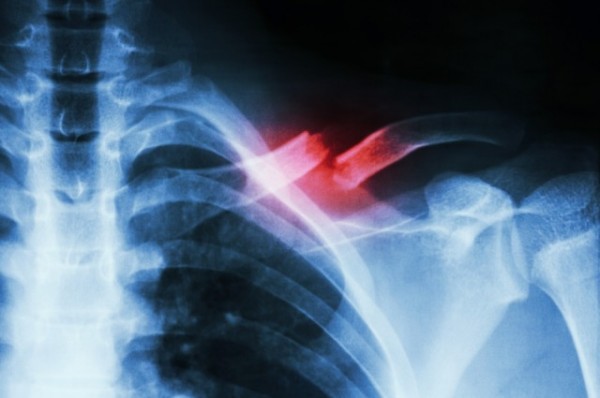

如果我们不再需要打着厚重的石膏,等待像是无穷止尽的数月之后才能让断骨愈合,这是不是很棒呢?或许,藉由材料科学的前瞻发展,我们正持续地朝此理想境界向前匍匐,好比说,在法国就有团队提出一种能注入骨头的发泡接合剂,不仅能帮助伤处恢复,还能促进骨质生成。

这种接合剂本质上具有多孔的渗透性,能让矿物质渗入亦能让废物析出,帮助骨头快速生成。但科学家所面临的问题是这些渗透孔都不够大,无法让骨头细胞深入患处,或是让治愈中的骨头长出新血管。

所以理想的CMC必须具有大小不一的渗透洞,这样才能帮助形成新骨,而且还富有弹性不会造成骨质疏松。但这谈何容易。任何一种用以制造大型渗透孔的材料除了必须能适用于人体不会产出毒素外,还不能折损材质本身的功能性。此外,如果接合剂的渗透孔过多,也可能因为长时间浸泡于体液中而很快地分解。